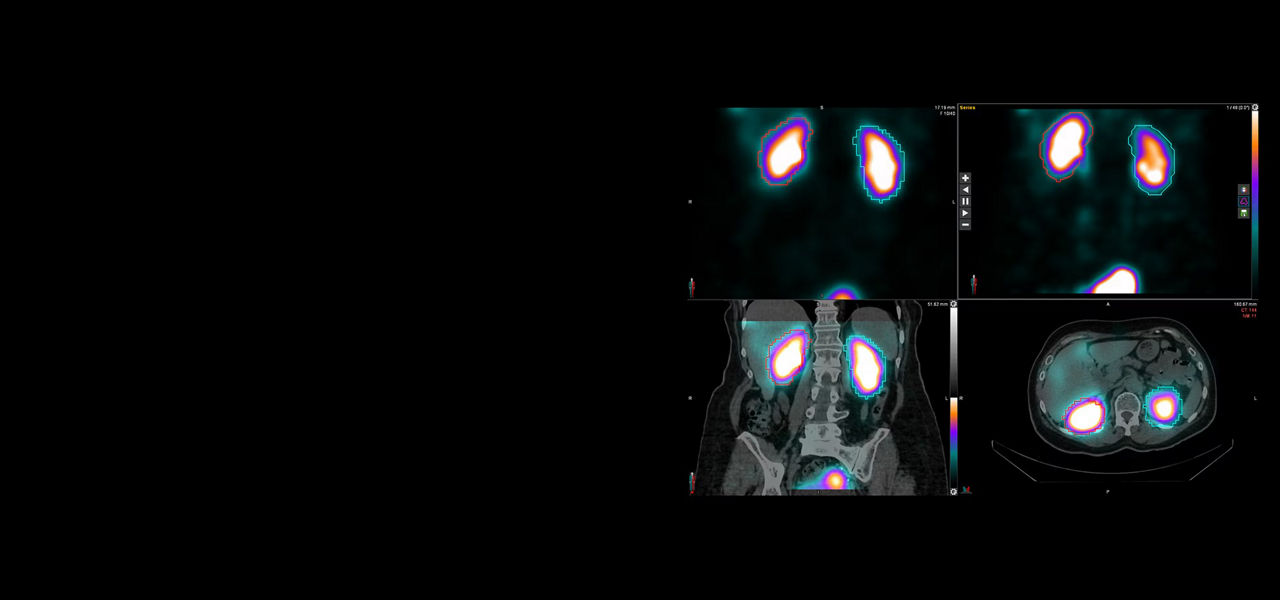

Make StarGuide, with its proven performance, the cornerstone of your theranostics practice as you build up or build out to meet the influx of these advanced procedures. StarGuide, with its optimized collimator design, allows clinicians to perform fast, dual-peak ¹⁷⁷Lu 3D whole body SPECT/CT exams with exceptional lesion detectability and high quantitative accuracy to help you make the personalized care decisions that are at the heart of theranostics. StarGuide is a future-defining catalyst helping SPECT technology push the promise of theranostics forward.

StarGuide’s ability to adjust the proximity of the detectors to the patient’s body as closely as possible, and from all necessary angles, leads to remarkable image quality, volume sensitivity⁵, as well as spatial and energy resolutions. The high-energy resolution enables clinicians to perform dual isotope examinations. The native 3D design streamlines workflows, in the pursuit of eliminating the need for additional acquisitions, as is often the case with conventional 2D gamma cameras. For theranostics, StarGuide enabled acquiring vertex to mid-thigh ¹⁷⁷Lu post-therapy SPECT/CT bone scans with 4 bed positions at 3-minutes/bed and a total scan time of 12 minutes.¹ Rapid whole-body scanning time like this is an important factor in helping improve patient comfort and enabling the patient to remain still during the entire exam.